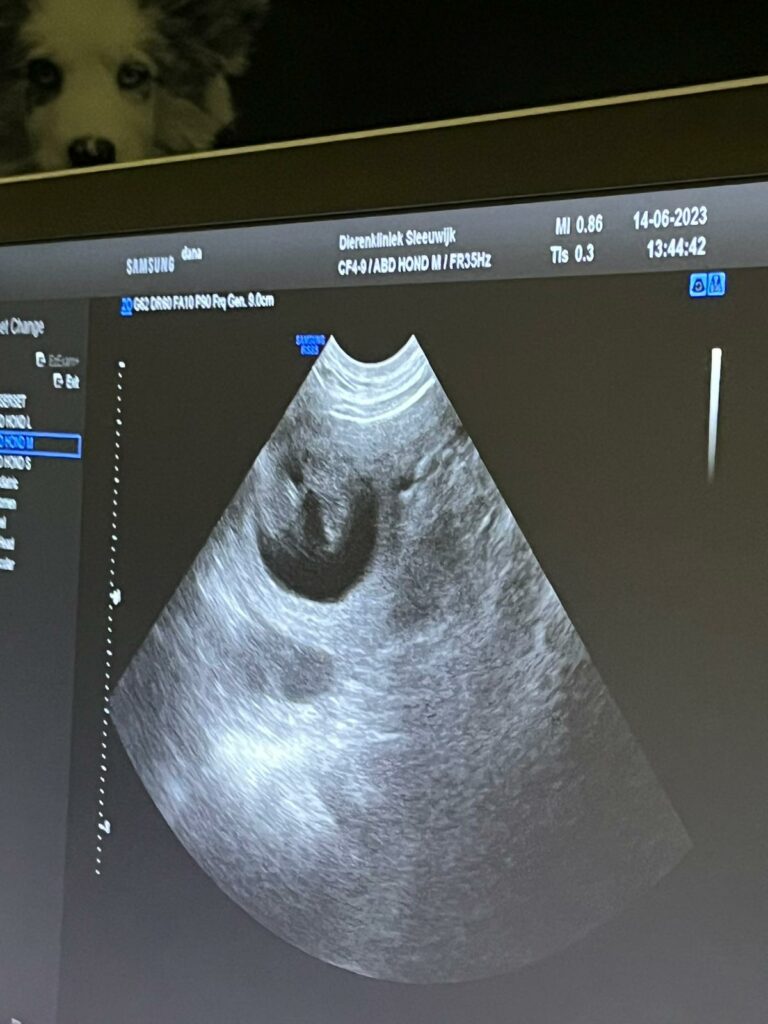

Vandaag was dan eindelijk de echo om te zien of Mildred daadwerkelijk drachtig is en al meteen zagen we pupjes in beeld verschijnen!! Fantastisch!! Ik was er niet helemaal zeker van, zij was de vorige keer de hele dracht ziek, nu heeft ze nergens last van. At ze de vorige keer nagenoeg niets, nu heeft ze voortdurend zin in met name lekkere dingen….. zag wel dat de tepels dikker werden en voelde ook al een buikje…..maar ja, zij gaat meestal na de loopsheid de schijndracht in en dan hebben ze dat ook. Helemaal blij dus dat ze drachtig is en er een flink aantal pupjes voorbij kwamen. Dat hebben Gahan en Mildred super gedaan!! 🥰 Er wordt erg naar de pupjes uitgekeken, ook in Noorwegen is de blijdschap groot ❣